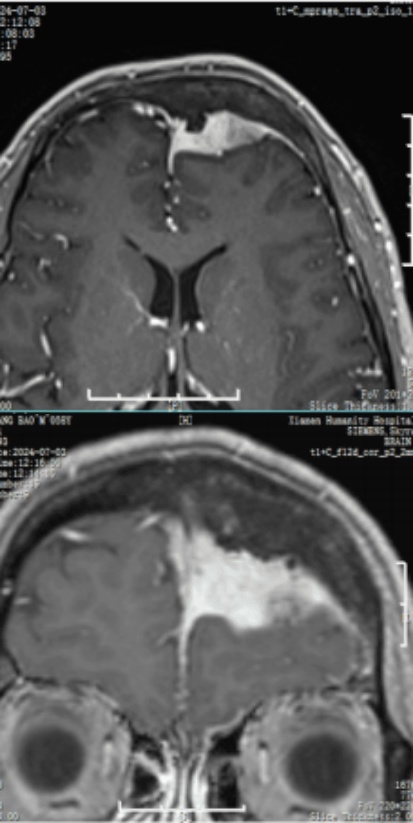

術后頭顱CT:腫瘤全切

術后頭顱MR:腫瘤全切

術后結果

術后所見